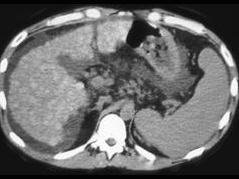

问题 男,15岁,进行性肢体震颤,肌张力增高,实验室检查尿铜125μg/g,CT检查如图,应诊断为 ( )

选项 A、肝血色素沉着症 B、结节性肝癌 C、肝硬化 D、肝转移瘤 E、肝豆状核变性

答案 E